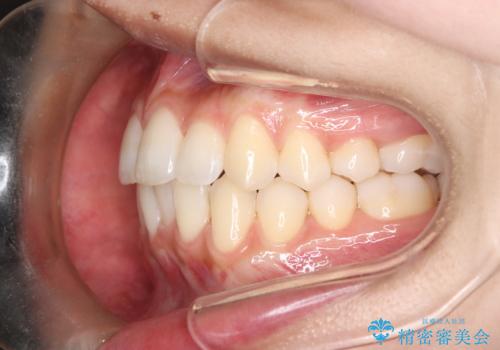

1年でここまで変わる。デコボコ歯並びの非抜歯矯正!

- 歯のデコボコ(叢生)を主訴にご来院された患者様です。

精密矯正検査を行った結果、歯を抜かずに行う、非抜歯のワイヤー矯正で治療を行う方針となりました。

歯並びの乱れに加え、**反対咬合(上下のかみ合わせのズレ)**も認められたため、見た目だけでなく、かみ合わせの改善も同時に行っています。

治療後は歯並び・かみ合わせともに大きく改善し、患者様にも大変ご満足いただけました。